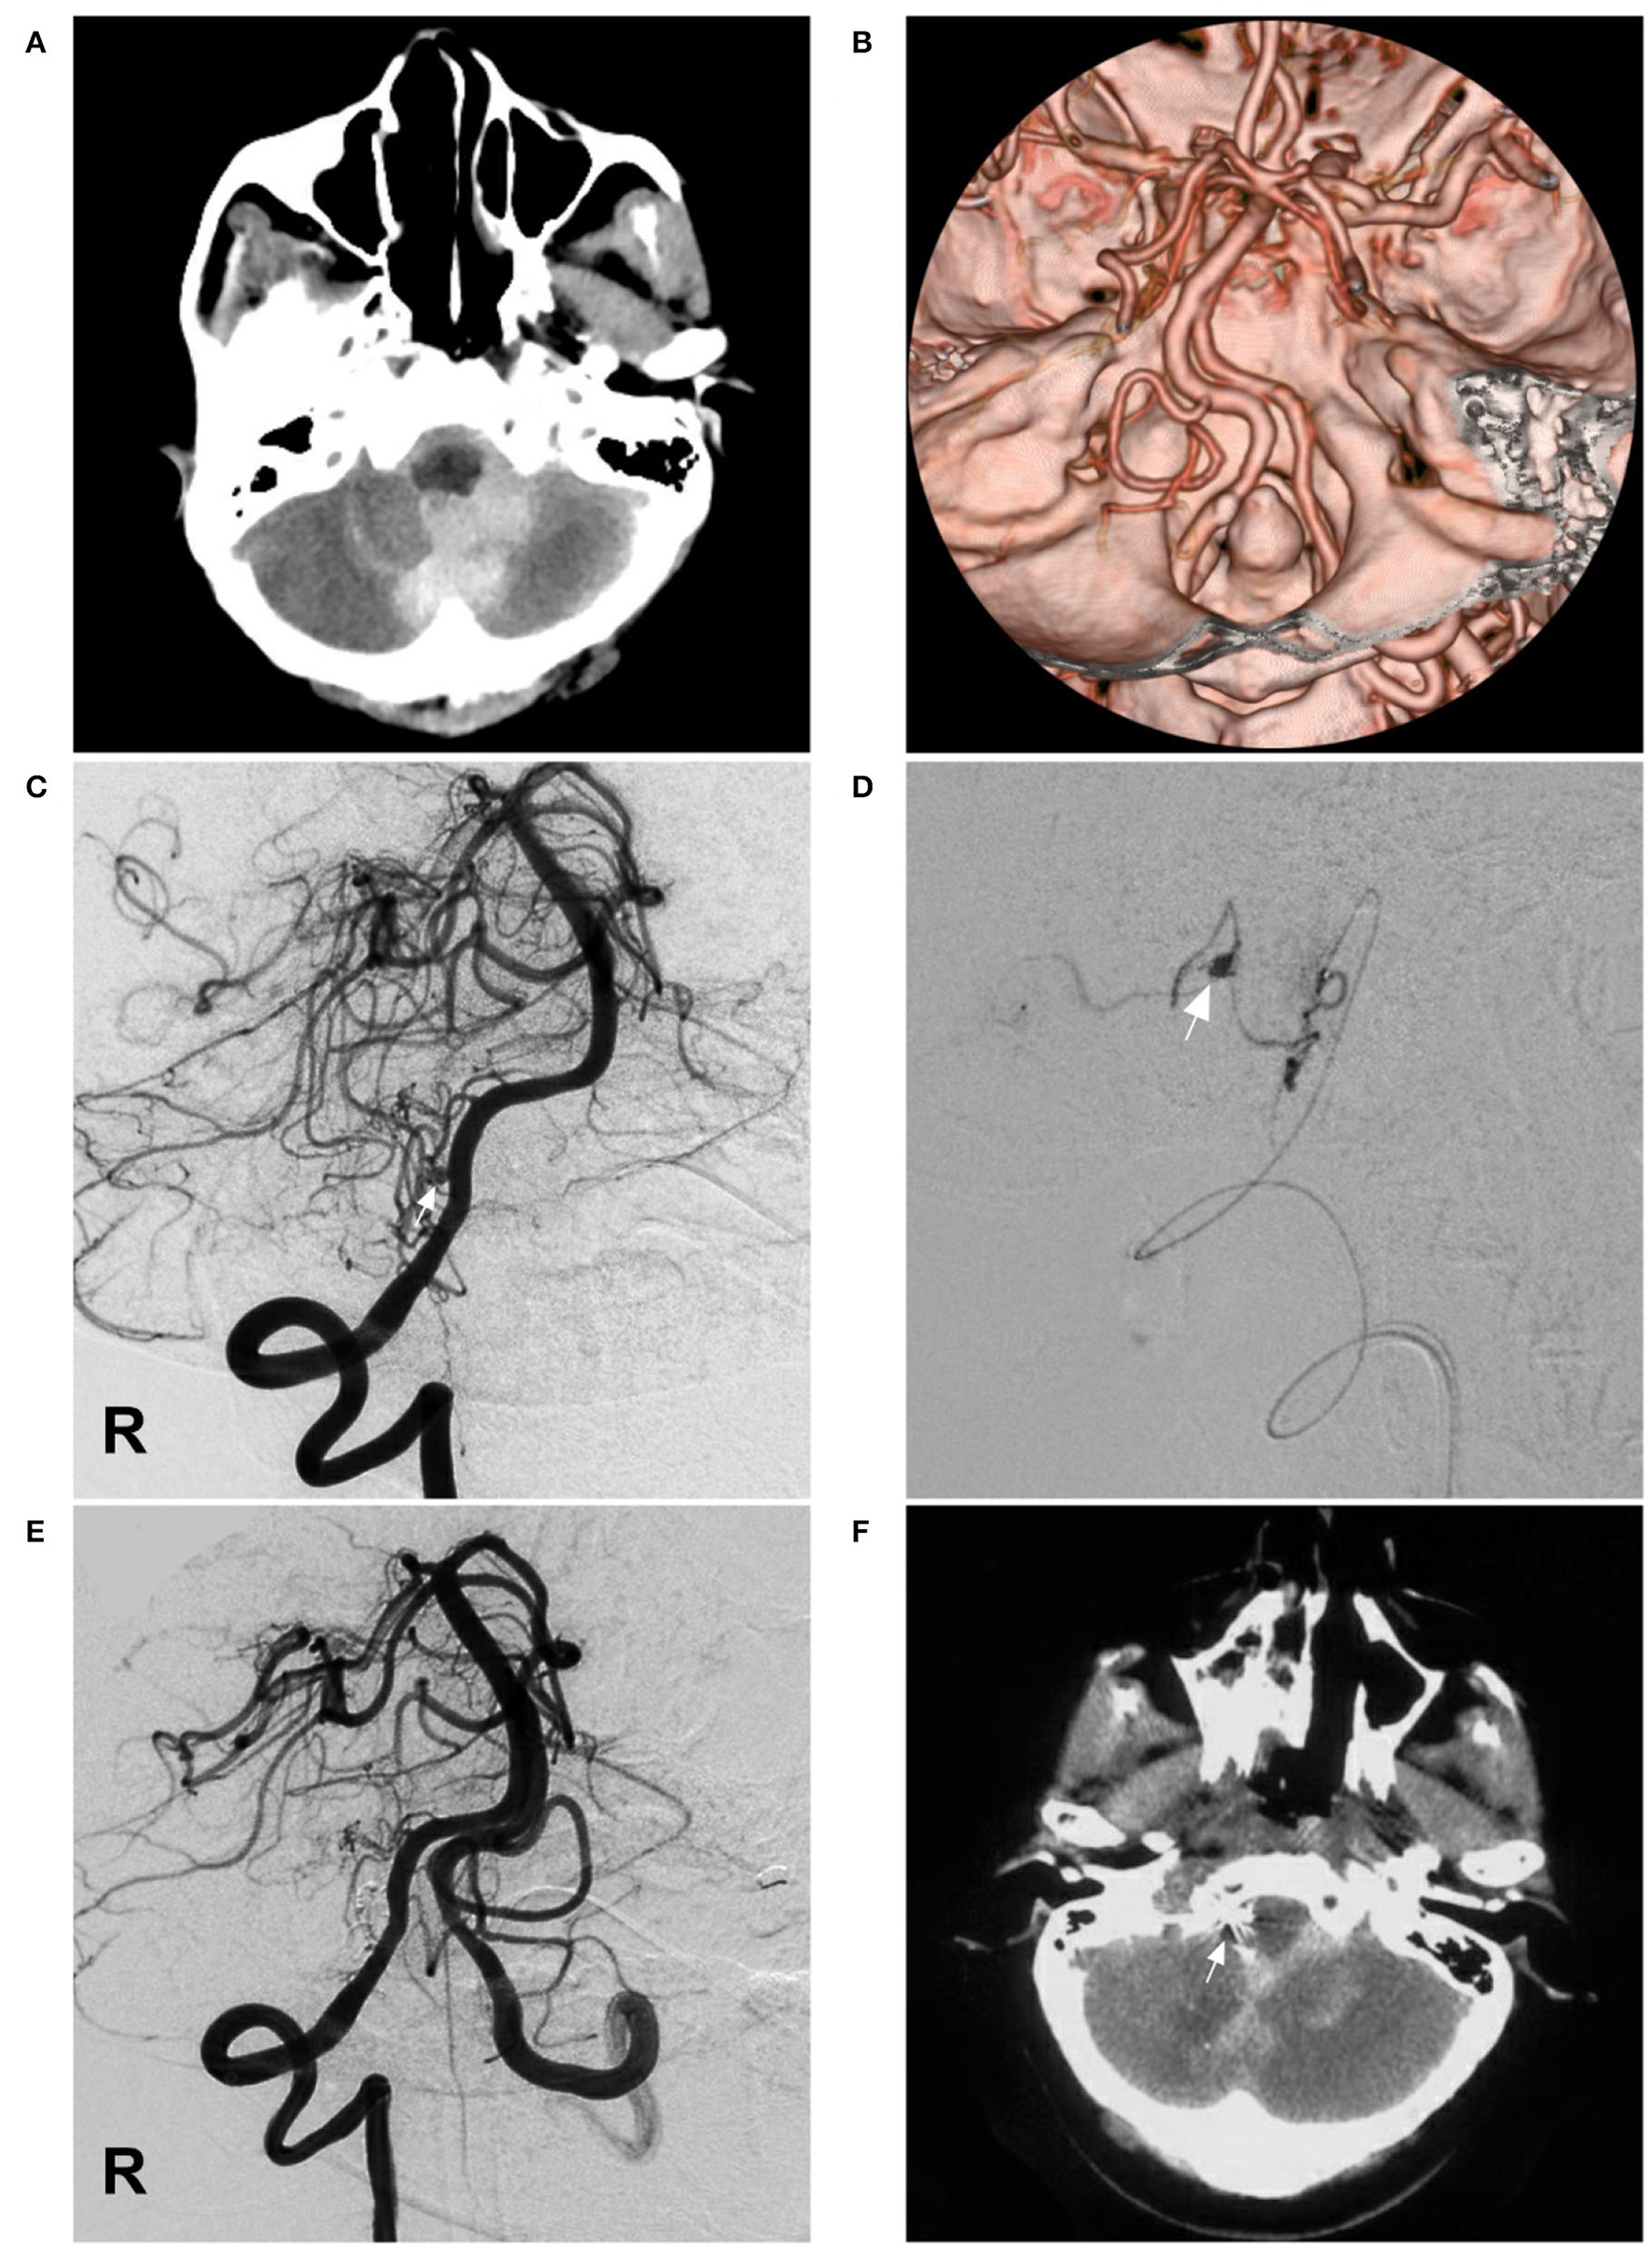

A 60-year-old female suffered a sudden onset of headache and vomited 3 h before admission. She was a Chinese patient of Han nationality and had a 10-year history of diabetes, but she had no history of drug abuse or surgical treatment of craniocerebral diseases. On physical examination, she was drowsy. The strength of the four limbs was normal. Head CT showed SAH concentrated at the cisterns around the brainstem and cerebellomedullary cistern (Figure 2A). CTA revealed no vascular abnormalities that might be responsible for the SAH (Figure 2B). Catheter angiography showed that the right PICA was hypoplastic and plexiform. Multiple slim arteries originated from the right VA near the hypoplastic PICA. A pseudoaneurysm was detected in the plexiform PICA (Figures 2C,D). Her family had no similar disease.

Imaging of case 2. (A) CT shows SAH concentrated at the cisterns around the brainstem and cerebellomedullary cistern. (B) CTA reveals no vascular abnormalities. (C) Angiogram of the right VA shows a pseudoaneurysm (arrow) located in the hypoplastic and plexiform PICA. (D) Superselective angiogram of the right PICA showing the pseudoaneurysm (arrow). (E) Angiogram of the VA shows that the aneurysm and parent PICA were cast with Onyx, and other branches are visualized. (F) Postoperative CT scan shows the location of casting Onyx (arrow) and partial resolution of the SAH. CT, computed tomography; CTA, CT angiography; PICA, posterior inferior cerebellar artery; R, right; SAH, subarachnoid hemorrhage; VA, vertebral artery.

Occlusion of the aneurysm and parent PICA via EVT was planned under general anesthesia. A Marathon microcatheter was advanced to the parent artery of the aneurysm via the guidance of a microwire to access the aneurysm. Then, the Onyx liquid embolic system was cast, successfully occluding the aneurysm and parent PICA (Figure 2E). The patient was stable postoperatively and regained consciousness 1 week later. A head CT scan performed 8 days later showed partial resolution of the SAH (Figure 2F). She was discharged to a local hospital for rehabilitation. A telephone follow-up revealed that she died of pulmonary infection 1 month later at the local hospital.